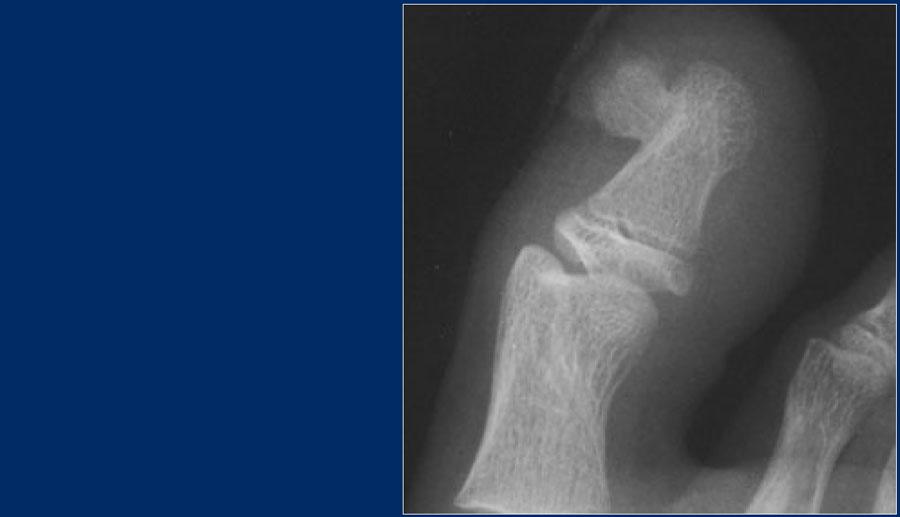

U Xương Sụn Bề Mặt (Osteochondroma)

U xương sụn là một phần xương nhô ra được bao phủ bởi một lớp mũ sụn.

Sự phát triển của u xương sụn diễn ra ở lớp mũ sụn, tương ứng với quá trình tăng trưởng sụn nội sinh bình thường tại các đĩa tăng trưởng.

Do đó, u xương sụn được phép phát triển cho đến khi bệnh nhân trưởng thành và các đĩa sụn tăng trưởng đóng lại.

Sự phát triển của u xương sụn ở độ tuổi trưởng thành, đặc trưng bởi mũ sụn dày (tín hiệu cao trên T2WI) cần làm dấy lên nghi ngờ về sự tiến triển thành ung thư sụn ngoại vi.

Here a patient with a broad-based osteochondroma.

Lưu ý rằng xương vỏ lan vào trong tổn thương.

Đặc điểm này giúp phân biệt nó với u cạnh vỏ xương.

Đây là hình ảnh bệnh nhân có u xương sụn diện rộng với sự kéo dài của vỏ xương vào cuống tổn thương.

Lưu ý phần ngoại vi thấu quang với các vôi hóa mờ nhạt.

Phần này tương ứng với vùng tăng tín hiệu trên chuỗi xung T2 có xóa mỡ ở bên phải.

Đây là biểu hiện của mũ sụn dày.